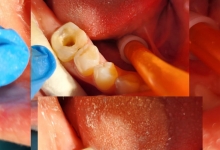

La Clinica LUY ESTHETIC ART tratamentul endodontic poate fi efectuat pe durata mai multor sedinte, doar cand chisturile dezvoltate sunt medii. Tratamentul nu este dureros deoarece se realizeaza sub anestezie. Pe langa talent, cunostinte medicale, dar si meticulozitate, acest tratament, presupune folosirea unei aparaturi performante:

– magnificatie (microscop)

– izolare cu diga

– tratament mecanic rotativ

– obturatie de canal tridimensionala prin folosirea unei tehnici de condensare la cald

– control radiologic.